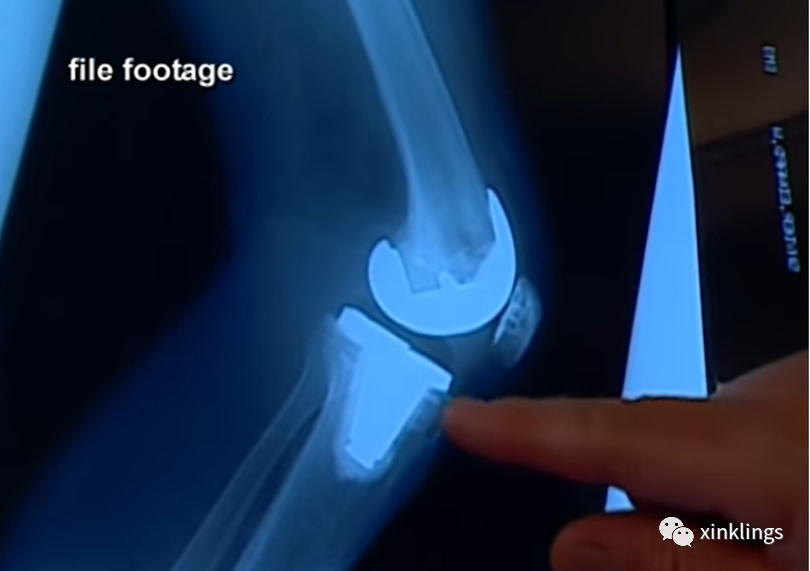

检方向庭上展示了薇琪膝盖的X光片,她右边膝盖的膝盖骨是人工的。据核实,薇琪在死前约18个月时动手术更换膝盖骨,罗恩承认那时他因为薇琪将饼干撒在地上对她动手施暴,致使薇琪膝盖骨粉碎,不得不装上人工膝关节。